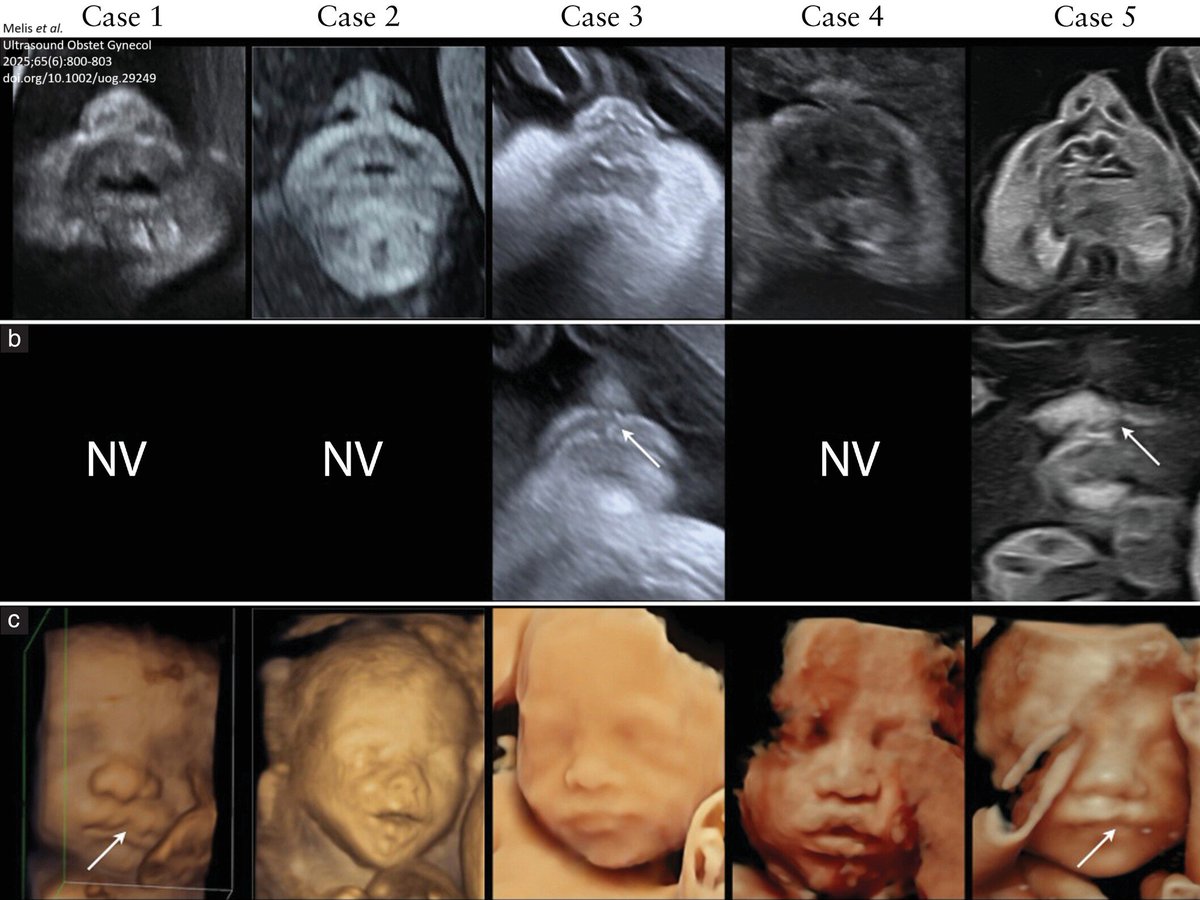

Letter to the Editor by Melis et al. in June #UOGJournal presents ultrasonographic features associated with five cases of isolated cleft lip on 2D and 3D prenatal ultrasound imaging, showing asymmetric appearance of the nostrils. bit.ly/4nazy5G